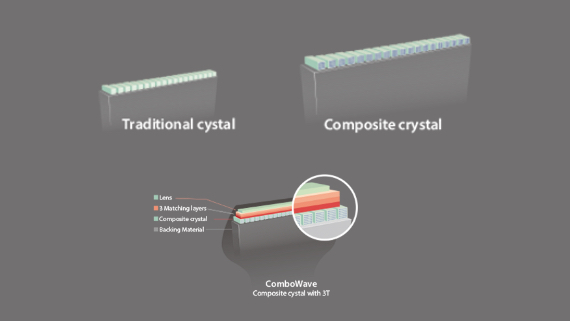

Echo Boost yang canggih

Terobosan beruntun Mindray untuk visualisasi gambar ultrasound terbaik.